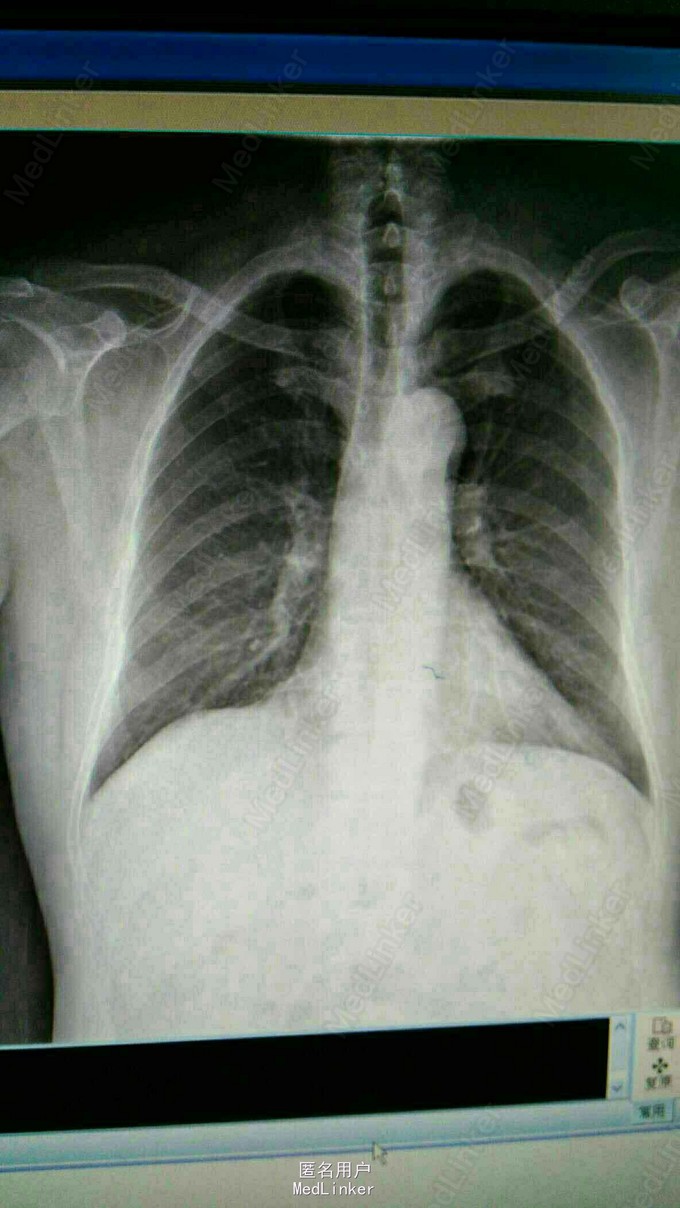

1、无痛性肉眼血尿10天

2、外院B超示:膀胱左侧壁可见一38x28mm低回声不规则包块,内见血流信号。现为进一步诊治,门诊拟以“膀胱占位性病变”收入我科。患者入院后双肾CTU及盆腔CT示:膀胱所见,考虑膀胱癌并累及全层;盆部、双侧腹沟股多发稍大淋巴结影 3、查体:腹平软,双侧上中输尿管点无压痛,膀胱区无压痛。双侧腹股沟区未触及肿物,尿道外口未见异常,阴囊无水肿,双睾丸可触及,肛周皮肤无红肿。直肠指检:肛门括约肌正常,前列腺不大,无触痛,表面光滑,质韧,边缘清楚,中央沟存在,未触及明显结节,指套未见染血。